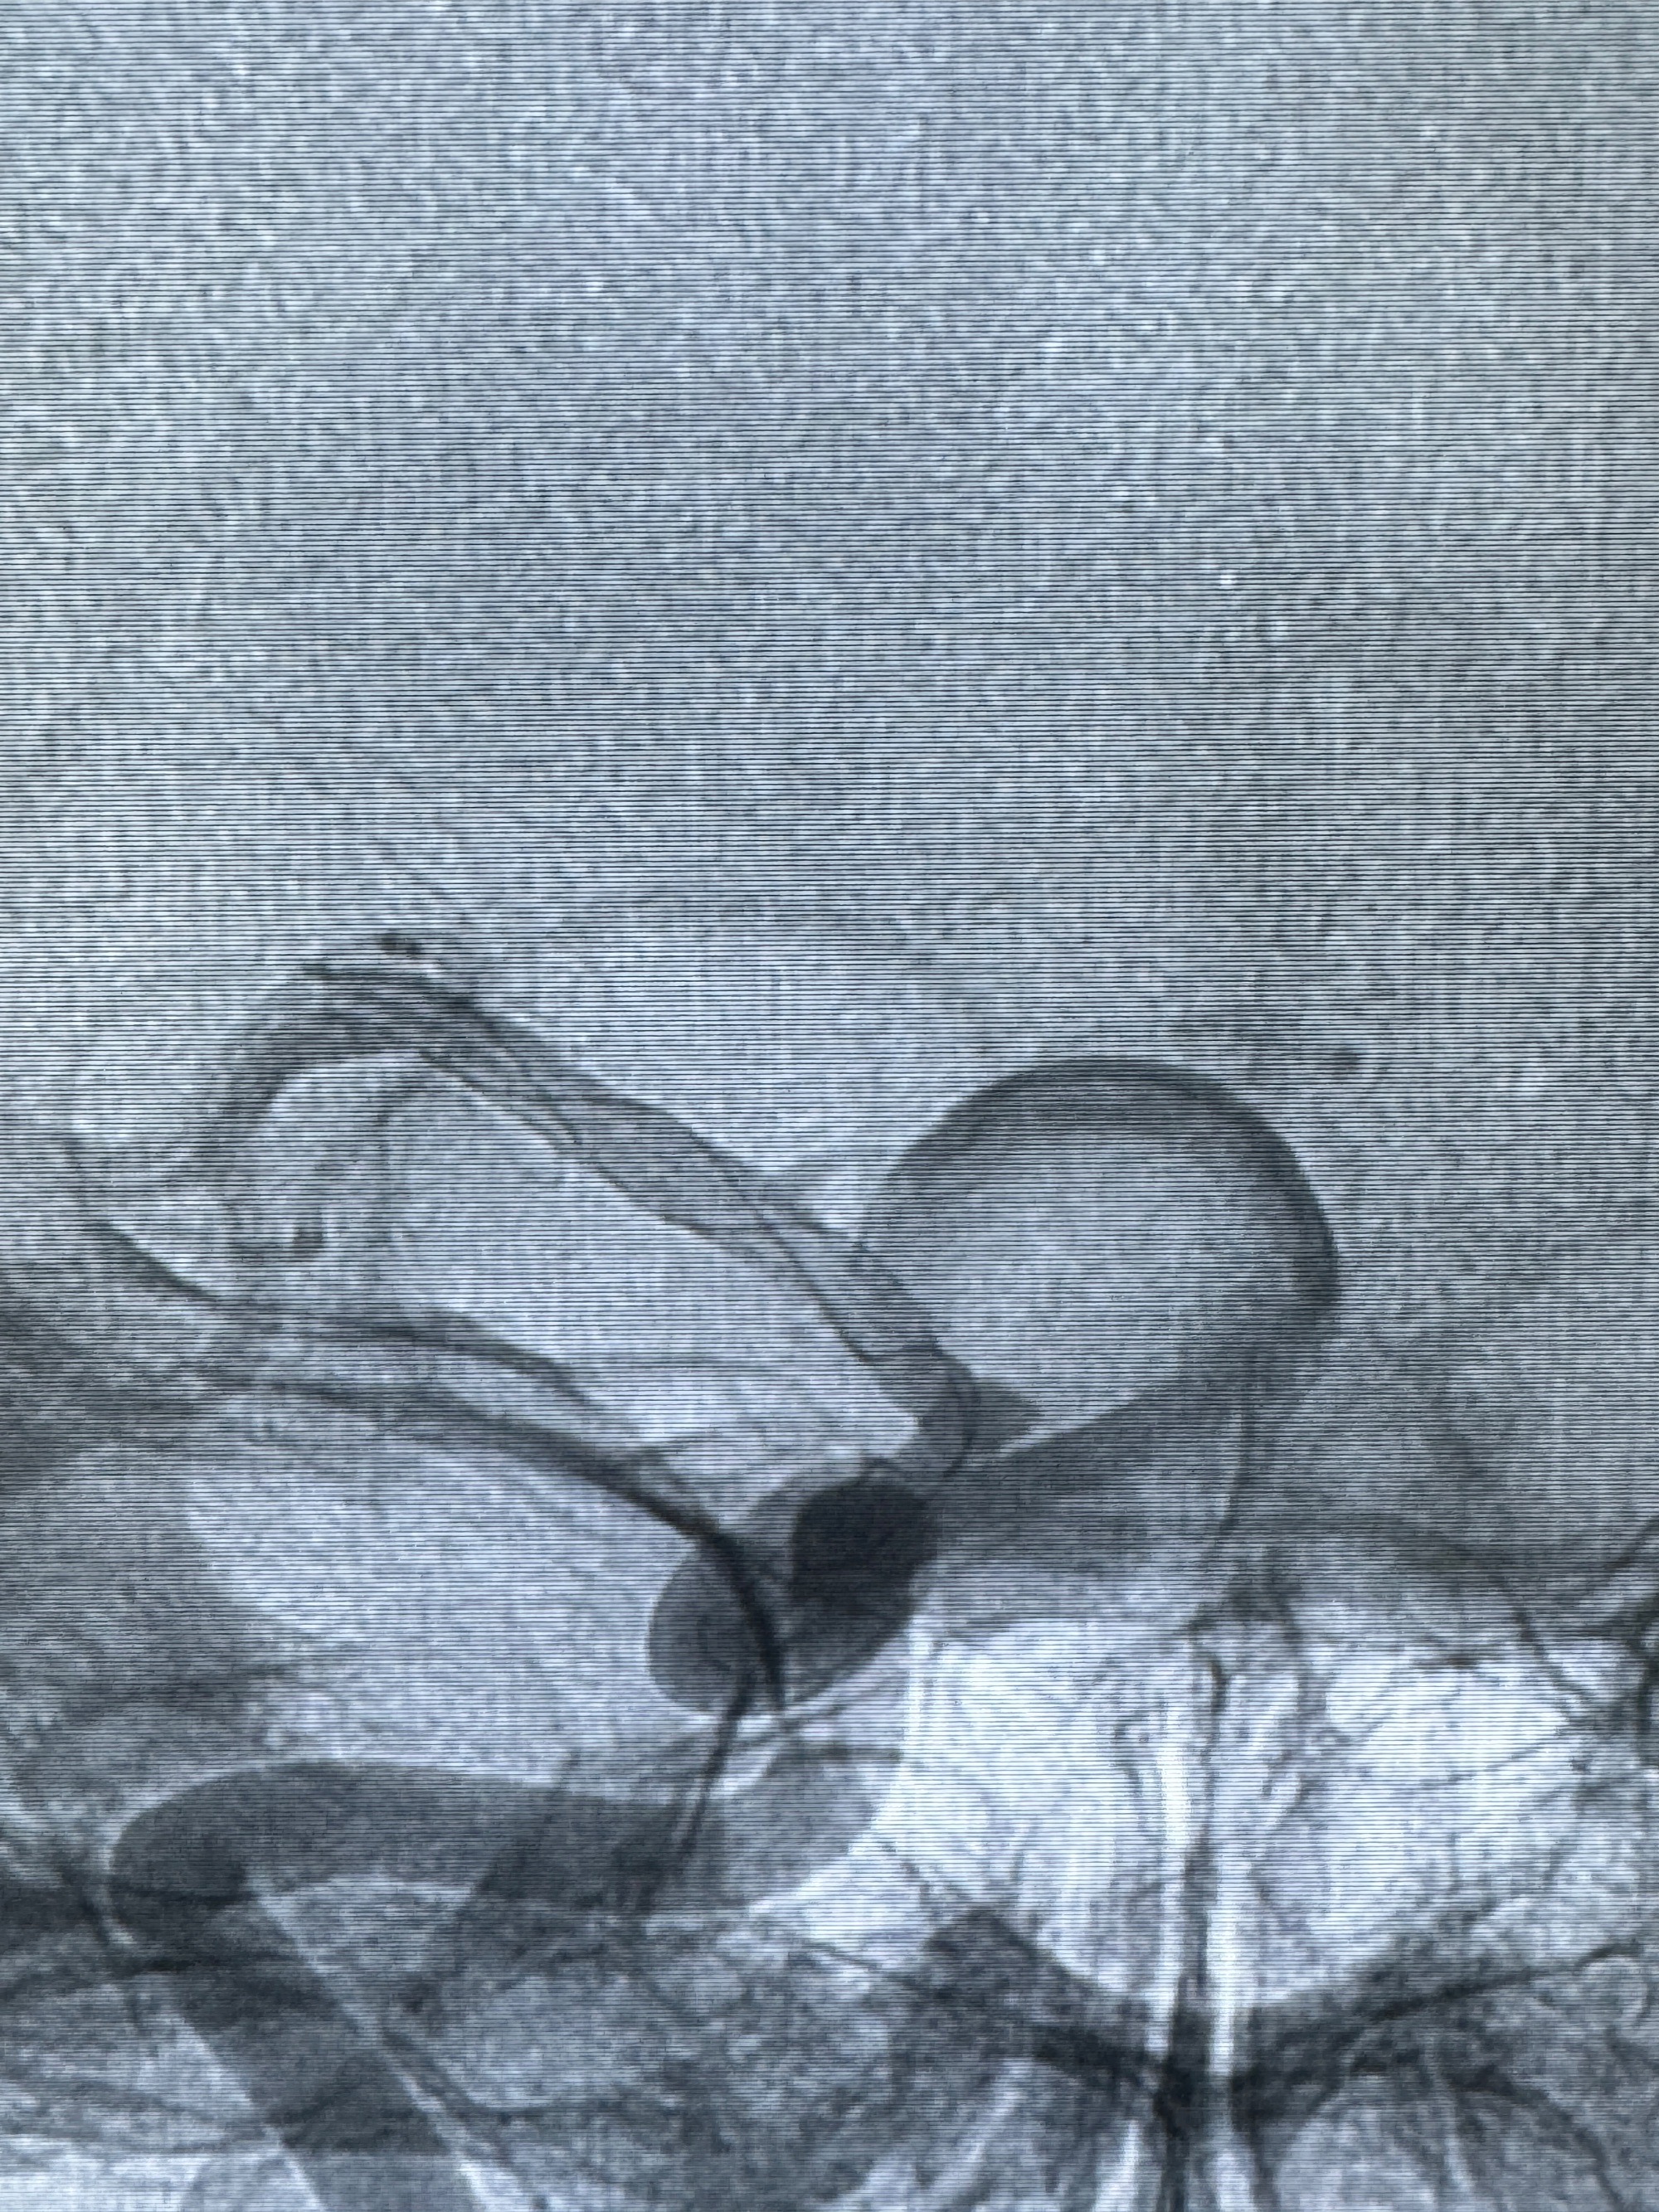

2023-12-08外院DSA:右侧颈眼动脉瘤,约13*12mm大小,压颈试验显示左右向及后向前代偿可

旋转3D展示动脉瘤局部的血管构筑

测量动脉瘤的大小:16*13.8*7.6mm大小,较原先变大,考虑双抗后瘤内血栓溶解可能

观察动脉瘤腔内的血流动力学情况